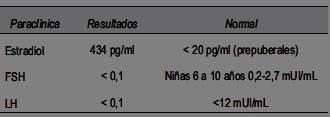

De la bioquímica se destaca el perfil hormonal gonadal con valores disminuidos de la hormona folículo estimulante (FSH) y hormona luteinizante (LH) (realizado con método ICMA), con asociación de estradiol elevado (tabla 1). La dosificación de la hormona tirotropina (TSH), tetrayodotiroxina (T4), prolactina y el factor de crecimiento insulínico tipo 1 (IGF1) se encontraban dentro del rango de normalidad para la edad y el sexo.

. Valores hormonales en sangre con estradiol alto y LH, FSH disminuidos.